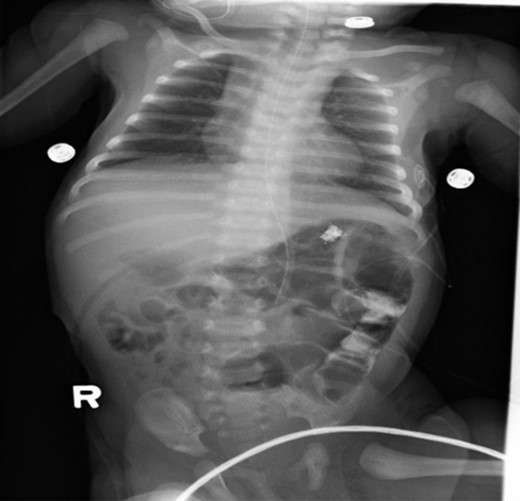

Postoperative care included monitoring in neonatal intensive care unit. Upper GI series (Figs 3 and 4) demonstrated no evidence of leakage. The patient tolerated a trial of pedialyte feedings and was subsequently discharged home.

Post-operative abdominal x-ray showing gas throughout the bowel and residual contrast in the descending colon.